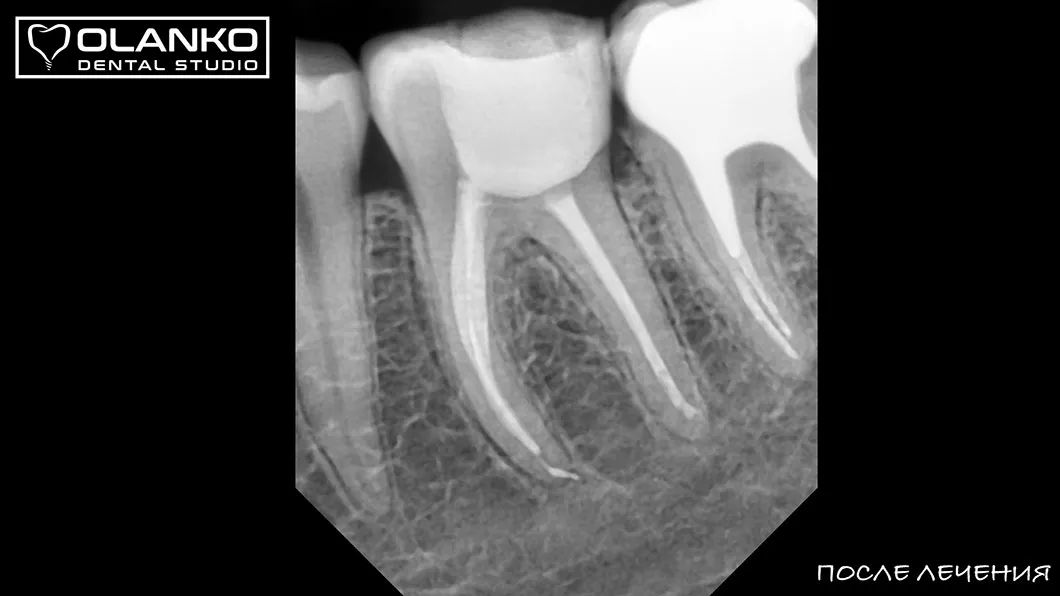

після

Для лікування простих клінічних випадків, як правило, потрібен всього один візит 1,5-2,5 години.

Складні випадки переліковування кореневих каналів, каналів зі складною анатомією, вимагають 2-3 візитів.

Ми маємо величезний клінічний досвід лікування зубів зі складною анатомією (викривленими, склерозованими каналами), а також повторного переліковування каналів з кістою, гранульомами, зламаними інструментами, з подальшими відмінними результатами загоєння хронічних запалень.